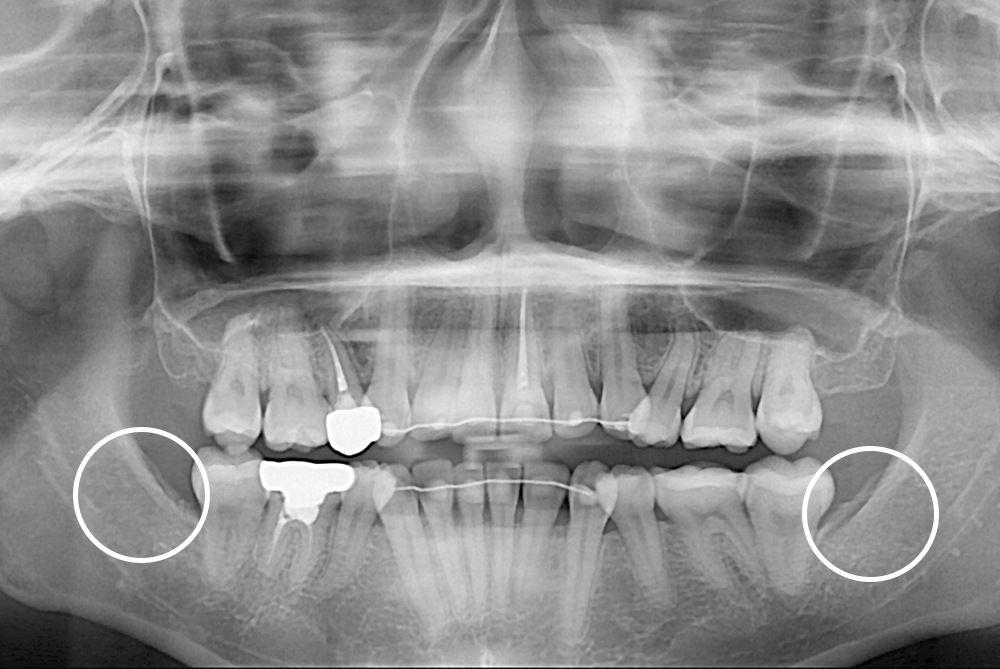

[사랑니] 매복 사랑니 발치

치료후 : 2020-06-26

세종치과는 구강악안면외과학 박사이신 원장님이 발치하는 치과입니다.